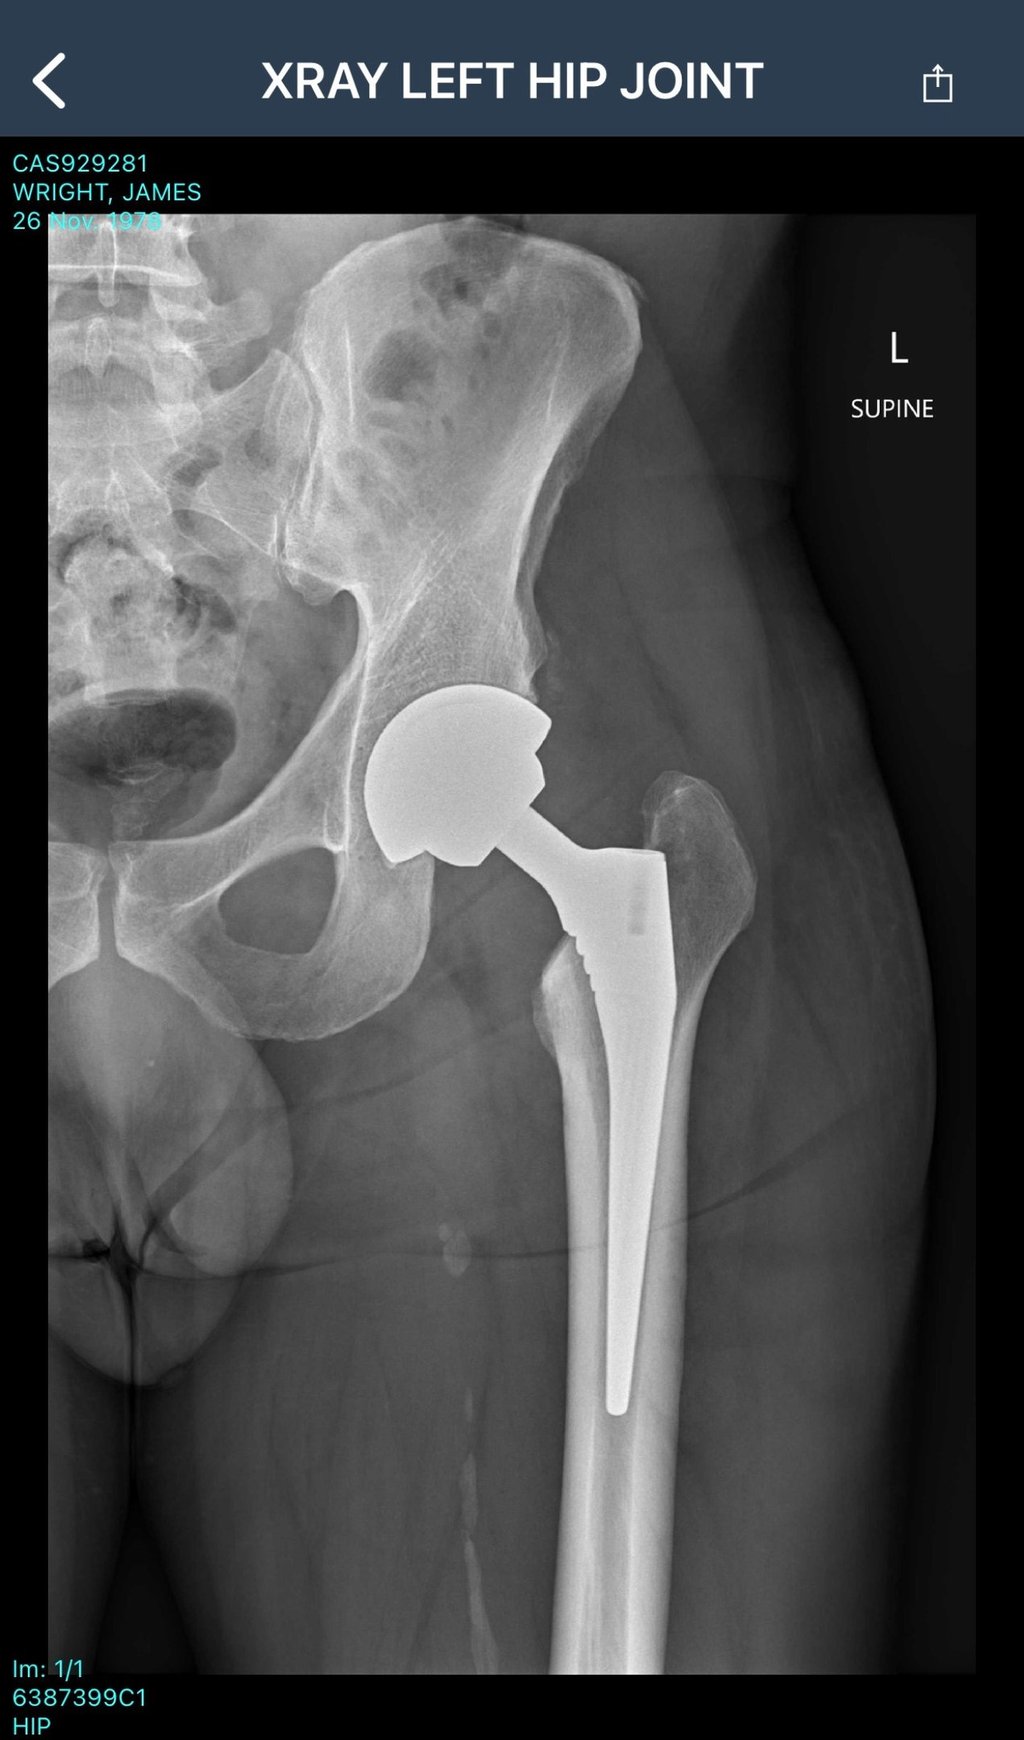

My neurosurgeon orders an X-ray of my hip.

The result isn’t vague. It isn’t “we’ll monitor it.”

It’s basically 100% certain: I need a hip replacement.

My first thought is brutally simple: I’m too young.

I’m 46 when I’m told. I turn 47 on 26 November.

Osteoarthritis sounds like one of those vague “getting older” diagnoses, but it’s actually pretty specific. It’s a type of joint wear-and-tear where the protective cartilage that helps bones glide smoothly starts breaking down. As that cushioning thins, the joint gets irritated and inflamed, movement gets stiff and painful, and the bones can start rubbing, or the joint mechanics can change in a way that makes everything worse. It’s bone on bone, and that’s not meant to happen.

In the hip, it can feel like deep pain, aching through the butt or thigh, stiffness after sitting, and a growing sense that walking is becoming work. When it gets severe enough, the “fix” isn’t more stretching or stronger painkillers; it’s replacing the joint surfaces entirely, which is exactly what a hip replacement does.